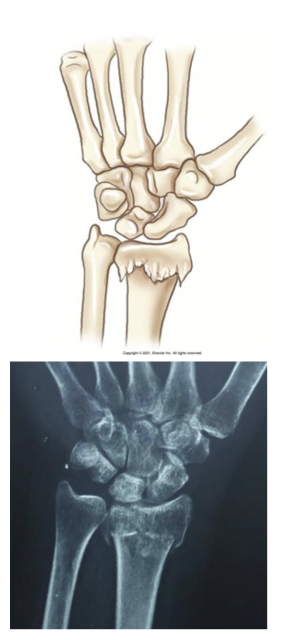

What type of fracture is this?

Colles - special fracture

What is a colles fracture?

Special

Fracture of the wrist in which distal radius is fractures with distal fragment displaced posteriorly

Smith (reverse colles) - special

What is a smith (reverse colles) fracture?

Fracture of the wrist with a distal fragment of the radius displaced anteriorly

Results from backward fall on outstretched hand (FOSH)